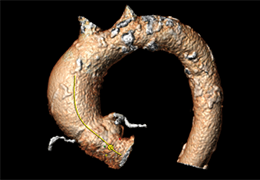

High-quality and fast 3D reconstruction and 3D rendering

Performs 3D reconstruction and volume rendering.